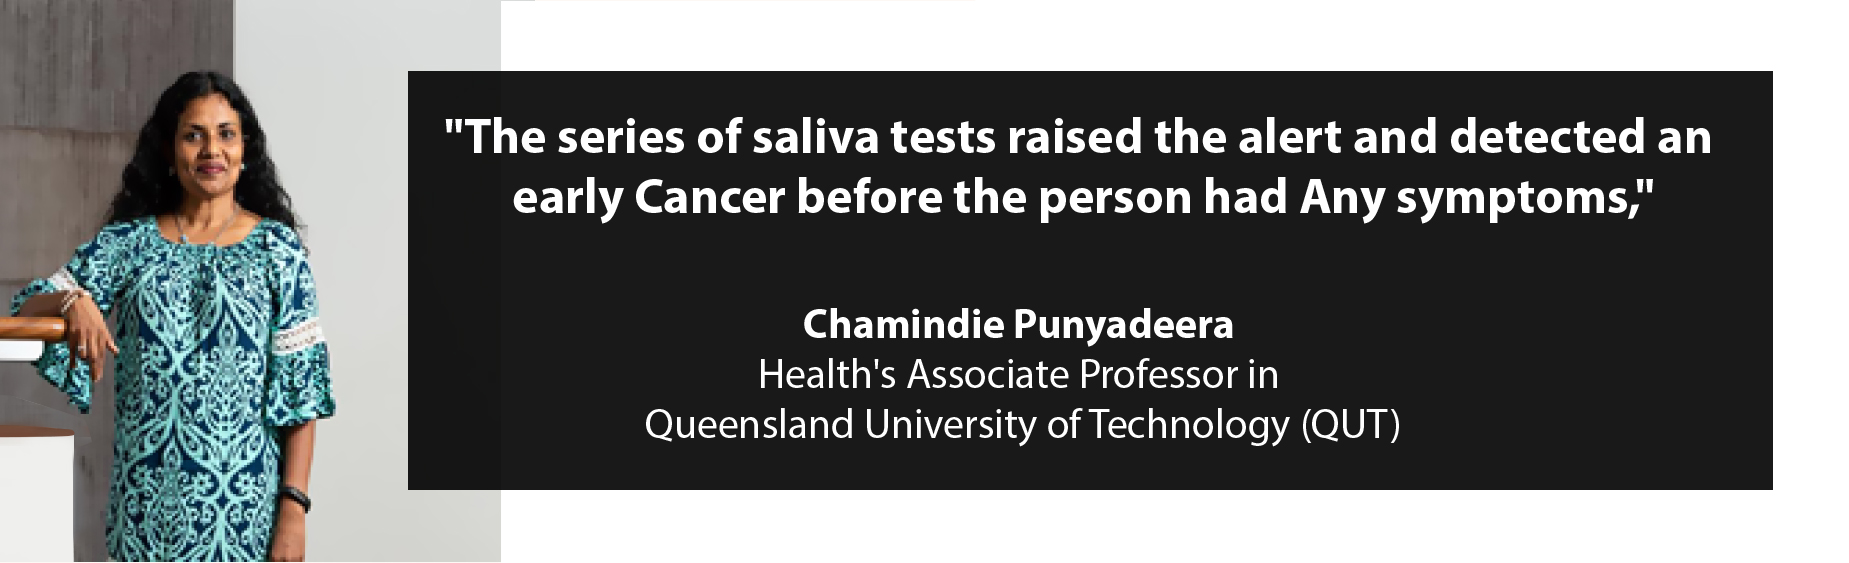

“The series of saliva tests raised the alert and detected an early cancer before the person had any symptoms,” said QUT Faculty of Health’s Associate Professor Chamindie Punyadeera, who, with Dr Kai Tang, developed the test. Professor Punyadeera said the discovery was made during an HPV-prevalence study which included 665 healthy individuals. The incidence of high-risk human papillomavirus (HPV)-driven throat cancers is on the rise in developed countries. Unfortunately, it is often discovered only when it is more advanced, with patients needing complicated and highly impactful treatment options. In the US, HPV-driven throat cancers have surpassed cervical cancers as the most common cancer caused by HPV. However, unlike cervical cancer, up until now, there has been no screening test for this type of oropharyngeal cancer.

be suspicious that there may be underlying cancer. “The person whom we reported in this study had been consistently HPV-16 DNA positive for 36 months, with a steadily rising count of HPV-16 DNA after testing at 6, 12 and 36 months. The patient was found to have a 2mm squamous cell carcinoma in the left tonsil, treated by tonsillectomy. This has given our patient a high chance of cure with very straightforward treatment. Since the surgery, the patient has had no evidence of HPV-16 DNA in his saliva.”

The presence of this pattern of elevated salivary HPV-DNA must be fully evaluated, as it may provide the critical marker for early cancer detection. Professor Punyadeera said this was the first-ever case of histologically confirmed diagnosis of an asymptomatic, hidden throat cancer, diagnosed with a saliva screening test and that wider validation studies are required to confirm this finding.